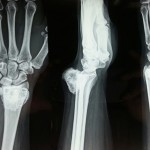

Image Quiz 10 #Wrist

What are your treatment options? Use the Poll and write your answers in the Comments section below. Popular Answer may not imply right answer. Follow our twitter handle for the right answer, https://twitter.com/drhiteshg/status/567308751305076736?s=01